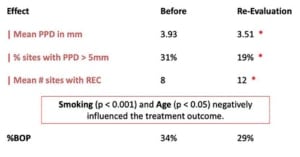

Belangrijk is om na stap 2 een evaluatiemoment te houden door middel van een parodontiumstatus, kijken hoe het fysiek, mentaal en financieel gaat met de patiënt en of de end-points bereikt zijn. Wanneer er een pocketdiepte is van onder <5 mm dan kan verder worden gegaan met stap 4, de nazorg. Wanneer dit niet bereikt is moet eerst stap 3 doorlopen worden.

In stap 3 wordt restontsteking getackeld door herhaalde subgingivale reiniging bij pockets van 4-5 mm en bloeding bij sonderen en daarnaast parodontale chirurgie bij pockets van meer dan 6 mm. In de lezingen wordt benadrukt dat het in de praktijk niet zo zwart-wit is en dat dit per patient en gebitselement bekeken moet worden.

Stap 4: Nazorg

Stap 4 bestaat uit nazorg waarbij eerst de situatie wordt beoordeeld. Het is ook belangrijk dat de patiënt zelf zorgt voor supragingivale plaquecontrole door middel van het begeleiden van de patiënt met het gebruik van een elektrische tandenborstel en cilindrische ragers. Het bijsturen van de motivatie en instructie is een belangrijk onderdeel van de nazorgbehandeling. Uiteraard wordt er een professionele gebitsreiniging uitgevoerd, sub en supragingivaal. Bloeding na sonderen is daarvoor een belangrijke parameter. Uiteindelijk voor een nazorg behandeling afgerond met polijsten en op inidctaie het aanbrengen van fluoride. Ten slotte wordt een recall interval wordt bepaald tussen 3 en 12 maanden. Belangrijke factoren om dit interval te bepalen zijn roken, diabetes, aantal pockets > 5 mm, BOP% en hoeveelheid botverlies. Om deze stappen binnen de nazorg goed te kunnen doorlopen en voldoende tijd te kunnen besteden aan alle aspecten is het zo genoemde “profy hour” bedacht.